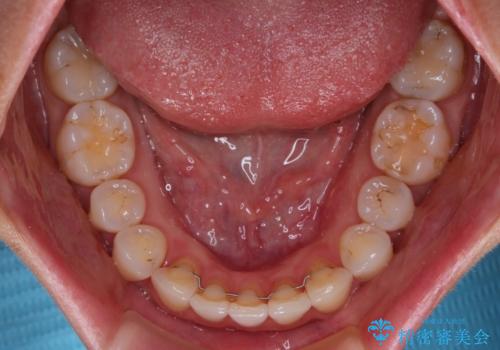

骨格的に上下正中がずれていたため、奥歯がしっかりと噛み合うか心配でしたが、ずれているなりに、しっかりとした咬み合わせとなりました。

- 捻れた前歯が飛び出しており、口が閉じにくいとのことで来院された患者様です。

出っ歯というわけではないものの、前歯の捻転により口唇が押し出されている状態でした。

親知らずを抜去し、歯列全体を後方に移動させつつ、IPR(歯と歯の間を削る)でスペースを獲得し、インビザラインを用いて叢生を解消しながら前歯の突出を改善することとしました。